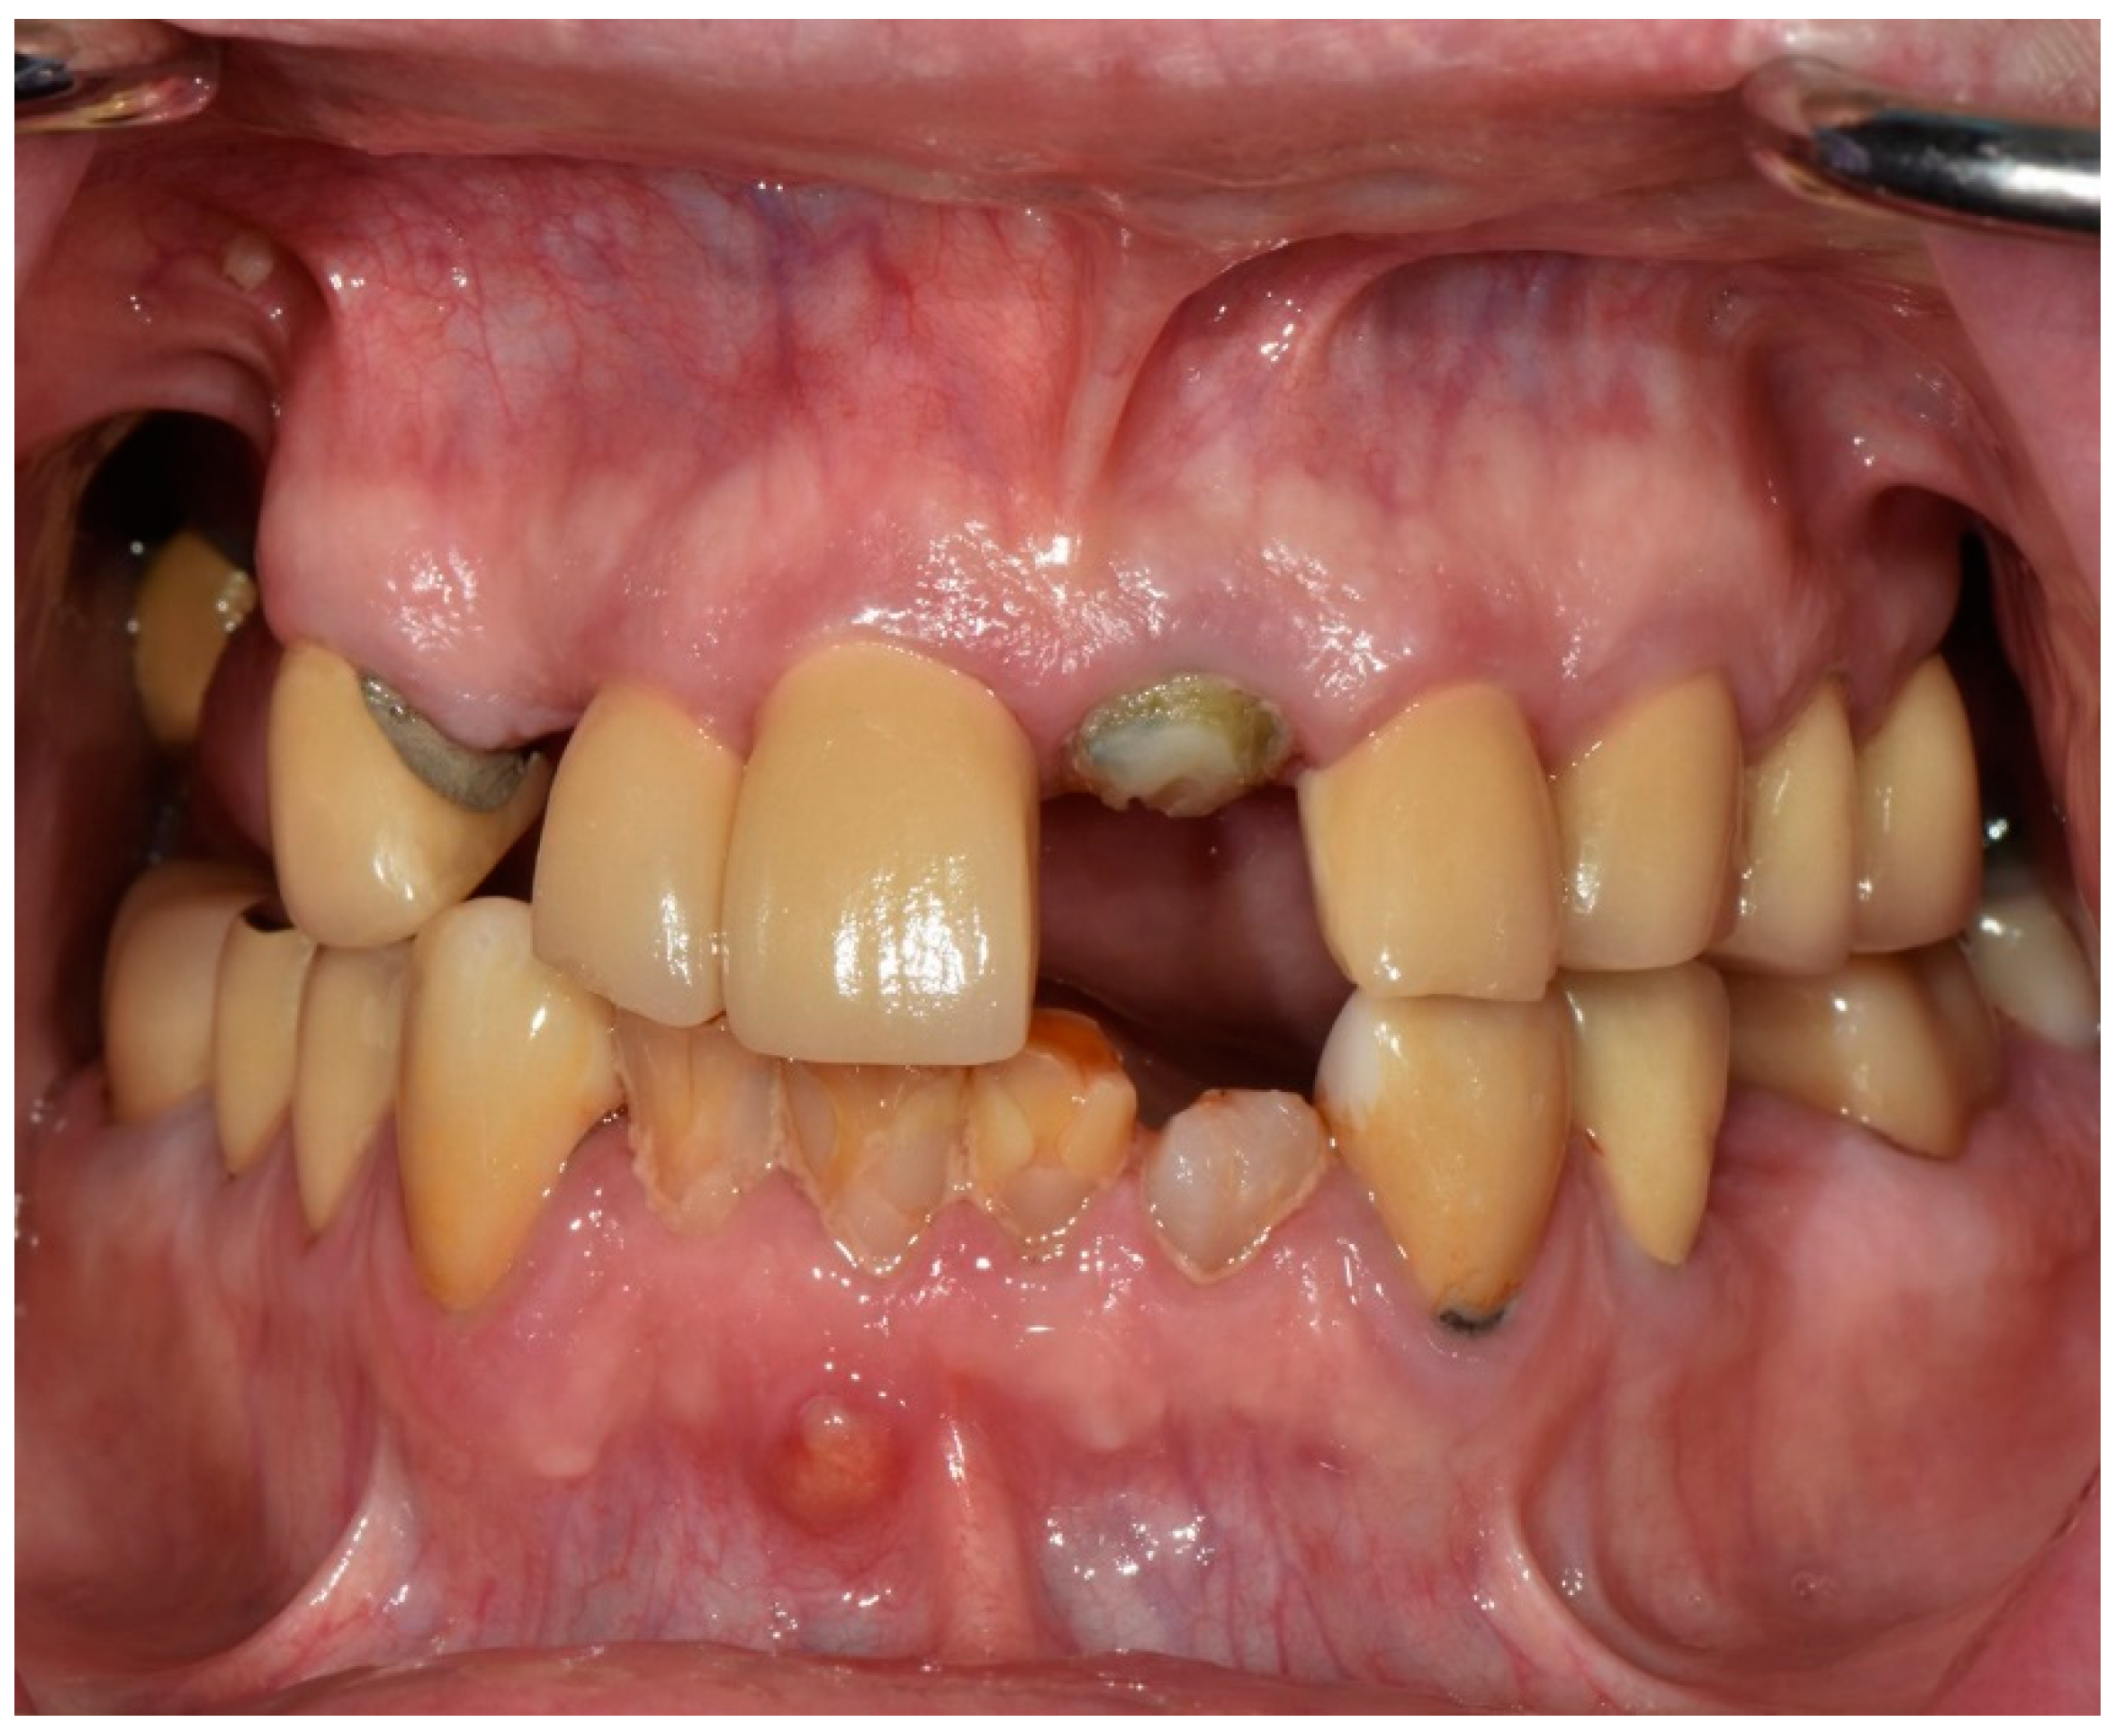

Intraorally, all the remaining teeth except for the mandibular incisors had complete-coverage extracoronal restorations, the majority with secondary decay. A sinus tract was noticed on the buccal mucosa of tooth number 4.1, and tooth number 1.1 presented a horizontal fracture above the gingival margin (Figure 2). Additionally, clinical features typical of Sjogren’s syndrome, including minimal salivary flow and generalized bleeding on probing, were also noted during the examination.

Figure 2.

Frontal intraoral photograph taken at the initial appointment.